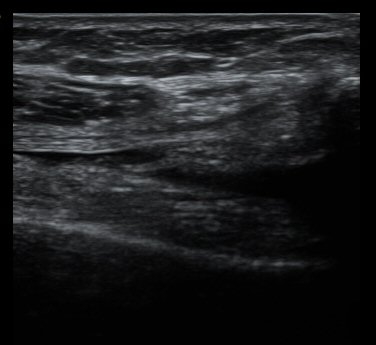

¹«¸­ ³»ÃøºÎÀδë Á¾´Ü¸é°Ë»ç¿¡¼­ ³»ÃøºÎÀδë Ç¥Ãþ±ÙÀ§ºÎ Àú¿¡ÄÚ ºÎÁ¾ ¹× ½ÉÃþ±ÙÀ§ºÎ ºÎºÐÆÄ¿­ÀÌ

°üÂûµÊ(±×¸² 3, 4).

¹«¸­ µÚ¿¡¼­ °üÂûÇÑ ÈĹæ½ÊÀÚÀÎ´ë °æ°ñºÎÂøºÎ¿¡¼­ ƯÀÌ ¼Ò°ßÀ» º¸ÀÌÁö ¾ÊÀ½(±×¸² 5).

ÃÊÀ½ÆÄ°üÂûÇÏ¿¡ ½ÃÇàÇÑ ¿Ü¹ÝºÎÇϰ˻翡¼­ ¾à°£ÀÇ ºÒ¾ÈÁ¤¼ºÀÌ °üÂûµÊ(÷ºÎ µ¿¿µ»ó).